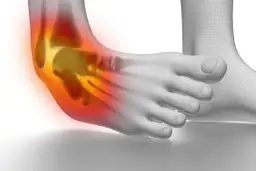

Skręcona kostka nie wymaga nastawienia w tradycyjnym sensie, ponieważ nie wiąże się z przemieszczeniem kości. Skręcenie to uraz, który dotyczy głównie więzadeł oraz innych tkanek miękkich, a staw zazwyczaj powraca do swojego pierwotnego układu. Głównym celem leczenia jest stabilizacja oraz odpowiednia rehabilitacja, aby przywrócić pełną sprawność. Próba samodzielnej manipulacji kostką może prowadzić do poważniejszych uszkodzeń, dlatego ważne jest, aby zrozumieć, jak prawidłowo postępować w przypadku tego urazu.

Skręcenie kostki to uraz, który występuje, gdy więzadła są nadmiernie rozciągnięte lub uszkodzone, podczas gdy zwichnięcie polega na przemieszczeniu kości w stawie. W przypadku skręcenia, objawy obejmują ból, obrzęk oraz ograniczenie ruchomości, ale kości pozostają na swoim miejscu. Z kolei zwichnięcie charakteryzuje się widoczną deformacją stawu i intensywnym bólem.- Skręcenie: ból, obrzęk, ograniczenie ruchomości, kości na swoim miejscu.